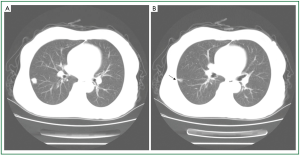

A 64-year-old female nonsmoker was admitted to our hospital because of chest pain without cough, hemoptysis, and other systemic symptoms. A chest CT scan revealed a peripheral solid nodule with a diameter of 13 mm in the lower lobe of the right lung (Figure 1A). The lesion did not present lobulated sign or spiculated sign, however, focal pleural indentation was observed (Figure 1B). From the CT scan, the diagnosis of lung cancer could not be excluded. Following wedge resection was performed. On gross examination, the tumor itself varied from grey to pale yellow. Microscopically, squamous and glandular epithelium could be observed, and in some area transitional epithelium like urothelium with morphology between the two kinds of epithelium was also present. Including transitional epithelium, all kinds of epithelium displayed papillary growth architectures (Figure 2A-C). The glandular epithelium consisted of non-ciliated columnar cells with eosinophilic cytoplasm and some mucin-filled cells (Figure 2B). In addition, the different epithelium showed no significant atypia, while some glandular tumor cells extended into adjacent bronchiolar and alveolar spaces with mucus which is similar to adenocarcinoma with lepidic-like pattern (Figure 2B). Further Immunohistochemical analysis showed these different components were diffusely positive for cytokeratin (CK) 7 (Figure 3A), CK19, CAM5.2, CK5/6 (the staining of the mucous cells were weak) (Figure 3B), and CK34βE12, but negative for CK20 or p16. The p63 staining showed immunoreactivity in the basal layer of glandular epithelium, and mostly in basal and parabasal layers of squamous and transitional epithelium. The different components were also positive for TTF-1, and in the squamous component, cells in the upper layers had weaker staining compared with that in the basal and parabasal layers (Figure 3C). The present case has been followed up for 24 months with no recurrence.